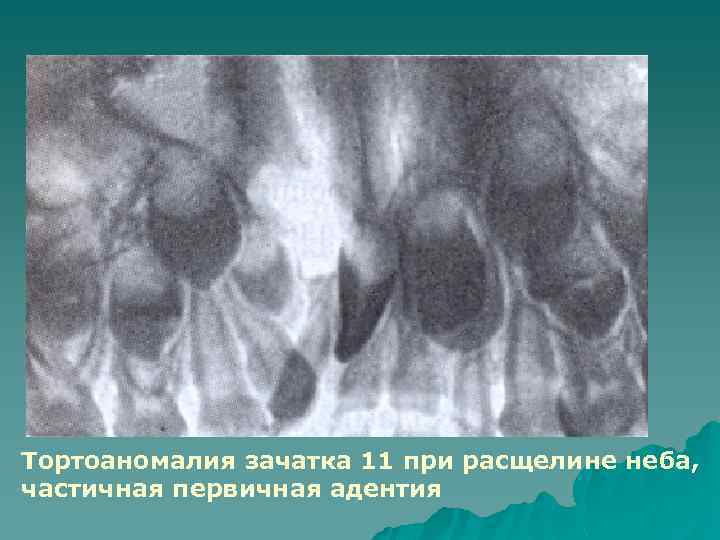

Тортоаномалuя - разворот зуба по вертикальной оси. Поворот зуба может быть разной степени - от нескольких градусов до 90 и даже до 180, когда зуб повернут небной стороной, например в вестибулярном направлении. Причины: недостаточность места в зубном ряду, неправильное положение зачатка зуба, наличие сверхкомплектных зубов, макродентия. Диагностируют при осмотре рта. Степень недостаточности места в зубном ряду и степень разворота зуба уточняют измерением на моделях. Взаиморасположение корней тортоаномального зуба и рядом расположенных определяют на ортопантомограмме.

Тортоаномалия зачатка 11 при расщелине неба, частичная первичная адентия